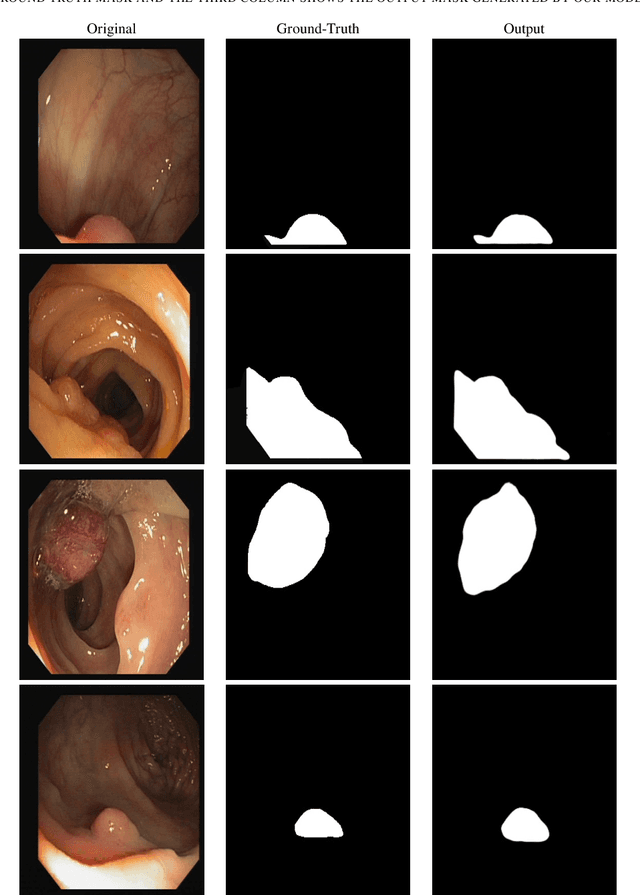

Abstract:Detecting and segmenting polyps is crucial for expediting the diagnosis of colon cancer. This is a challenging task due to the large variations of polyps in color, texture, and lighting conditions, along with subtle differences between the polyp and its surrounding area. Recently, vision Transformers have shown robust abilities in modeling global context for polyp segmentation. However, they face two major limitations: the inability to learn local relations among multi-level layers and inadequate feature aggregation in the decoder. To address these issues, we propose a novel decoder architecture aimed at hierarchically aggregating locally enhanced multi-level dense features. Specifically, we introduce a novel module named Dense Attention Gate (DAG), which adaptively fuses all previous layers' features to establish local feature relations among all layers. Furthermore, we propose a novel nested decoder architecture that hierarchically aggregates decoder features, thereby enhancing semantic features. We incorporate our novel dense decoder with the PVT backbone network and conduct evaluations on five polyp segmentation datasets: Kvasir, CVC-300, CVC-ColonDB, CVC-ClinicDB, and ETIS. Our experiments and comparisons with nine competing segmentation models demonstrate that the proposed architecture achieves state-of-the-art performance and outperforms the previous models on four datasets. The source code is available at: https://github.com/krushi1992/Dense-Decoder.

Abstract:Colonoscopy is a procedure to detect colorectal polyps which are the primary cause for developing colorectal cancer. However, polyp segmentation is a challenging task due to the diverse shape, size, color, and texture of polyps, shuttle difference between polyp and its background, as well as low contrast of the colonoscopic images. To address these challenges, we propose a feature enhancement network for accurate polyp segmentation in colonoscopy images. Specifically, the proposed network enhances the semantic information using the novel Semantic Feature Enhance Module (SFEM). Furthermore, instead of directly adding encoder features to the respective decoder layer, we introduce an Adaptive Global Context Module (AGCM), which focuses only on the encoder's significant and hard fine-grained features. The integration of these two modules improves the quality of features layer by layer, which in turn enhances the final feature representation. The proposed approach is evaluated on five colonoscopy datasets and demonstrates superior performance compared to other state-of-the-art models.